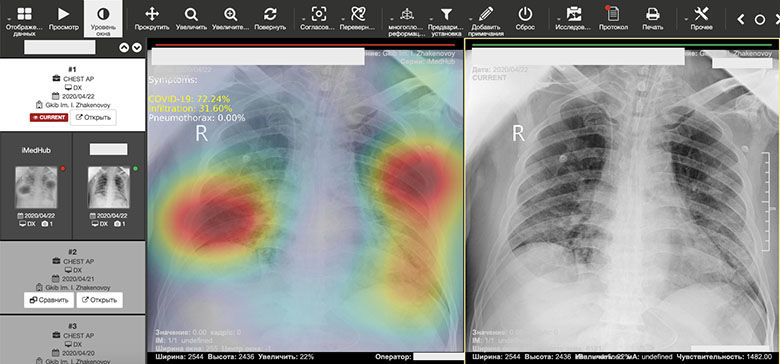

Для перегруженных и недоукомплектованных поликлиник появление нового решения в области искусственного интеллекта (ИИ) — «PneumoNet» — оказалось как нельзя кстати. В «PneumoNet» используются решения ИИ, обеспечивающие быстрое и точное выявление семнадцати наиболее патогенных заболеваний легких, включая пневмонию, туберкулез, рак и COVID-19. Система была разработана инновационным консорциумом Казахского научно-исследовательского института онкологии и радиологии и компанией Forus Data.

Интерфейс системы искусственного интеллекта PneumoNet.